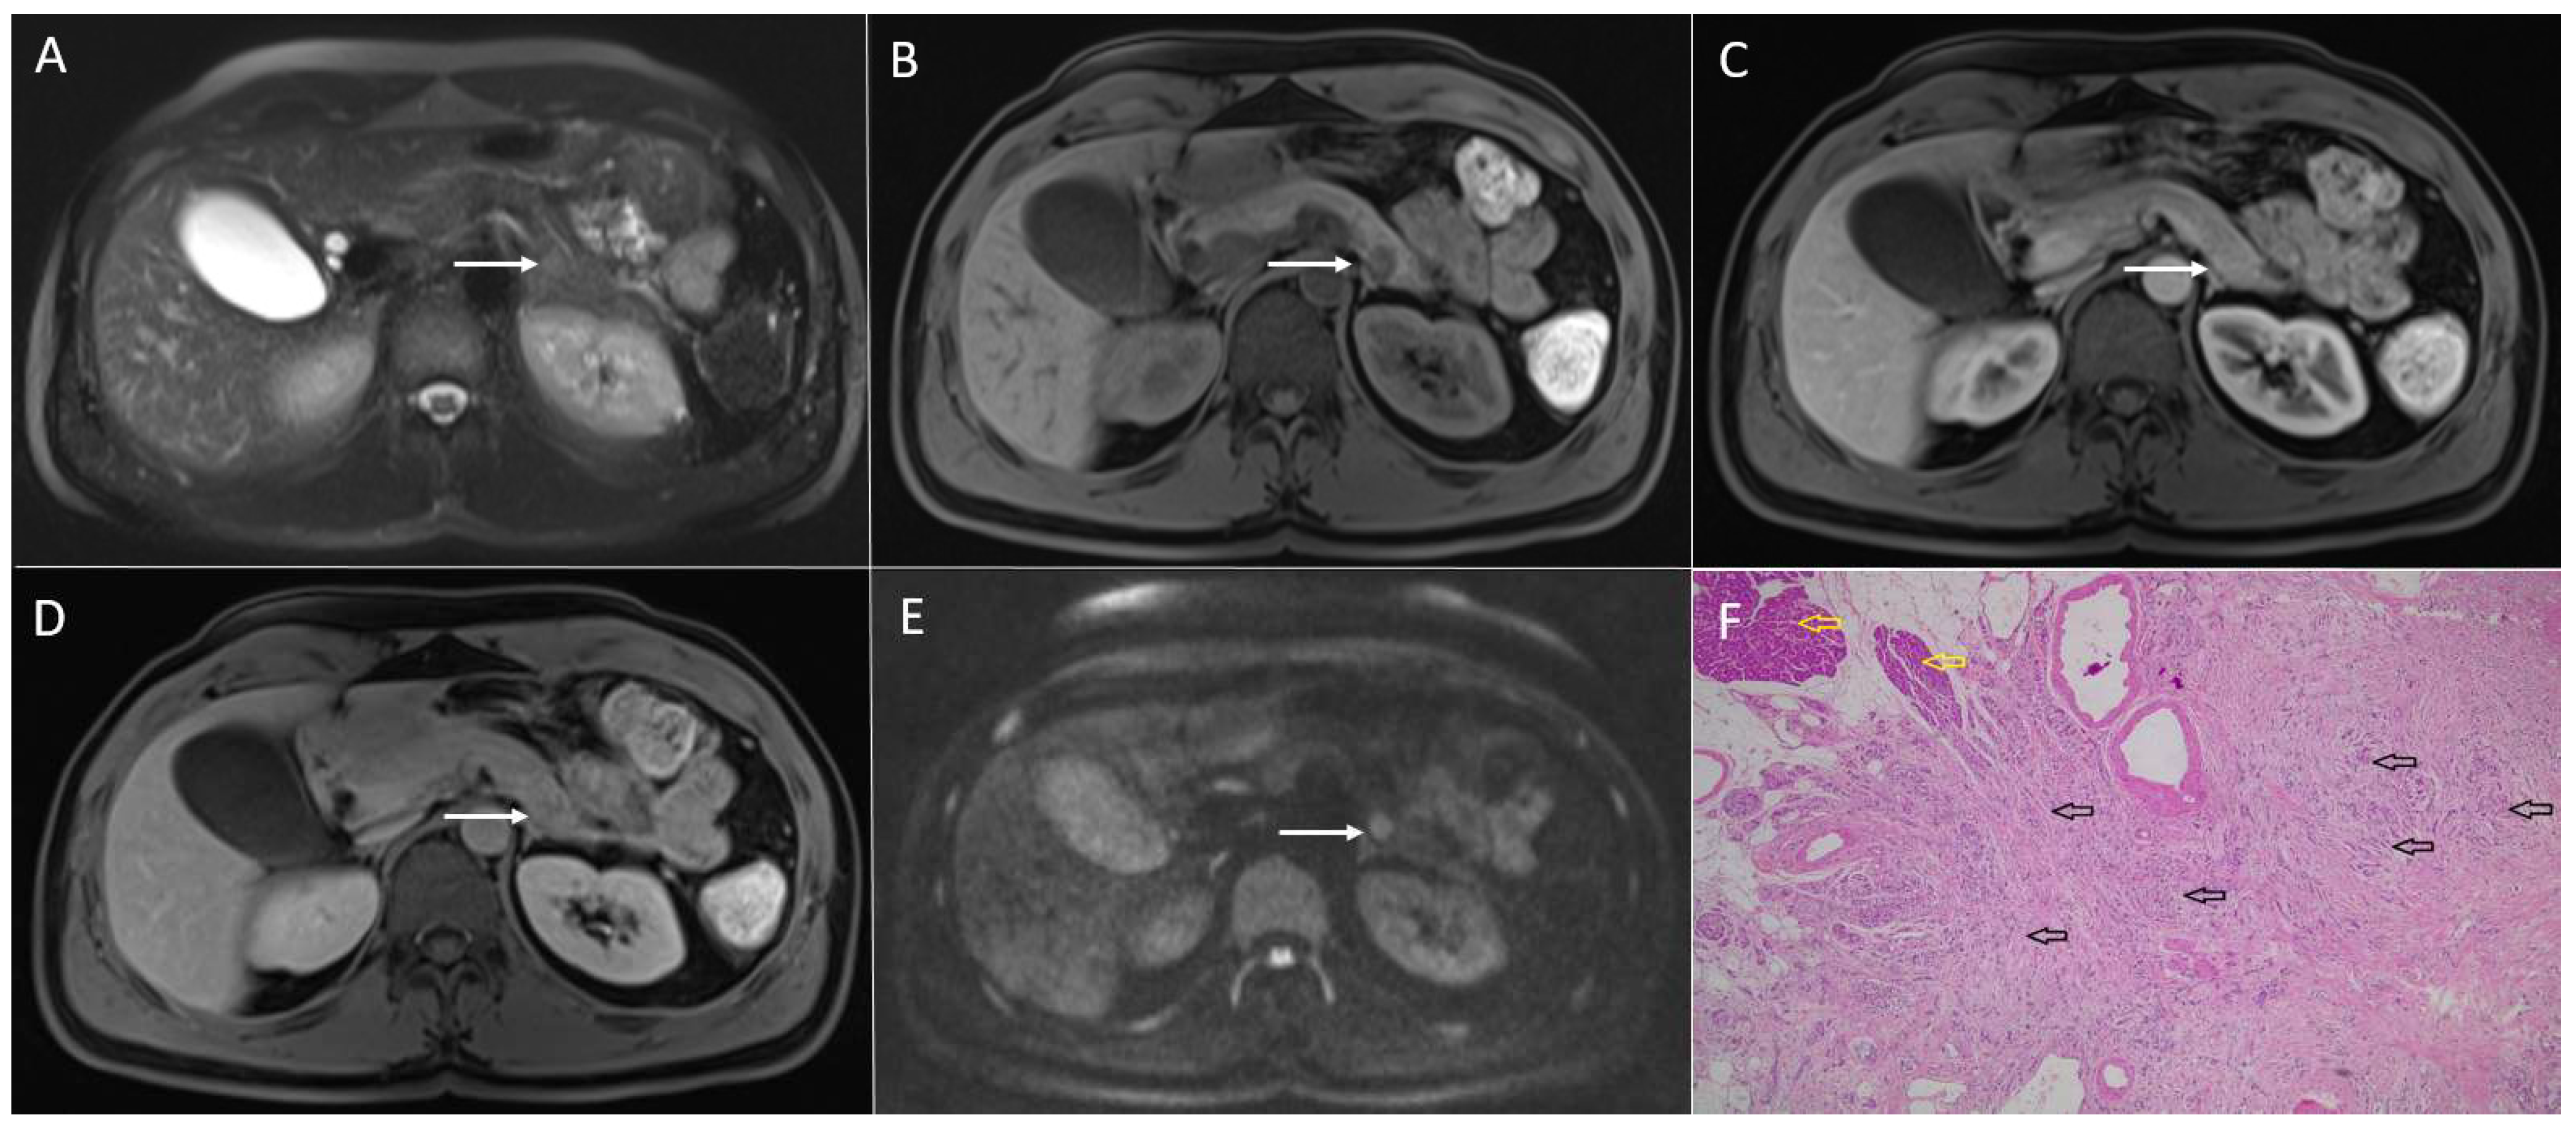

3.4. Pancreatic Metastases

4.1. Serous Cystadenoma

4.2. Mucinous Cystic Neoplasm